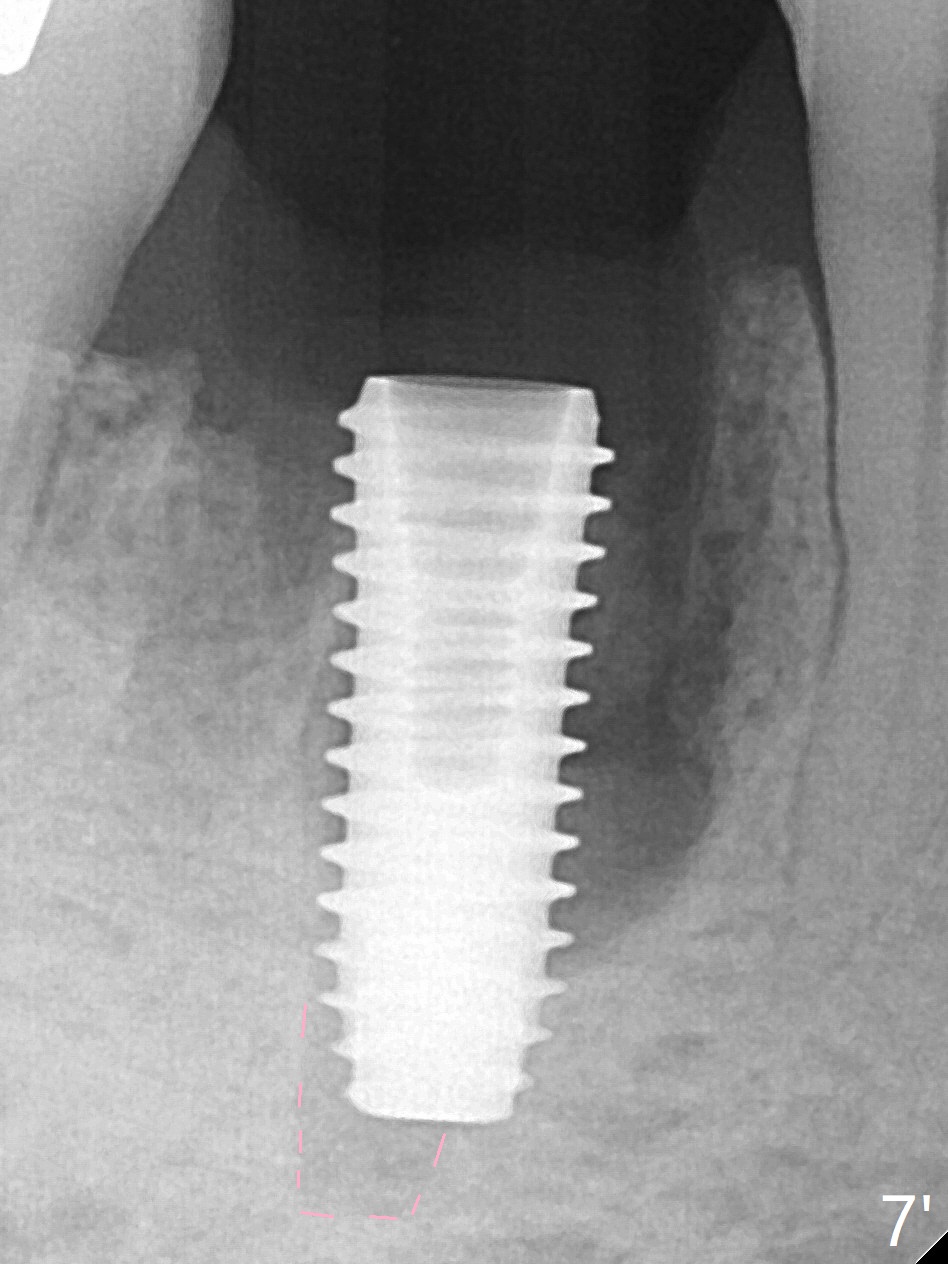

Preop oral Amoxicillin seems to be associated with reduction in the buccal and lingual (Fig.3 arrow) fistulae at #30, but there is mesiobuccal swelling (Fig.1 *) with 7 mm pocket (Fig.2). Osteotomy is initiated in the middle of the septum (Fig.3-5 S). As the osteotomy increases, it shifts mesially (Fig.6 arrow). Guided surgery is able to reduce shifting. A 5x13 mm implant is not seated completely (Fig.7) apparently due to osteotomy shifting. After removal of the bone from the osteotomy distally, the implant remains unseated with lower torque value (Fig.8). Following reuse of the 4.3 mm drill deeper by 1-2 mm, the implant is seated to a satisfactory depth (Fig.9 with increase in torque to 50 Ncm) with placement of Vera Graft (*) and a 7.5x4(3) mm abutment. After a second round of allograft placement (Fig.10 *), the implant is found to be 4 mm from the IAC. At the later stage of osteotomy, the coronal end of the septum is destroyed with loss of osteotomy depth landmark. It is apparent that the soft tissue landmark may be more reliable. The implant threads appear to be covered by the bone graft 3.5 months postop (Fig.11). The abutment is changed to 6.5x5(3) mm one before impression with minor margin prep. The bone density seems to increase 5 months postop, i.e., immediately post cementation (Fig.12) and 10 months postop (5 months post cementation (after retightening abutment), Fig.13 (*)). Periimplantitis develops mesiobuccally, consistent with bone loss 1 year 7 months post cementation (Fig.14 *); the implant seems to have been buccally placed. Bone graft is necessary with PRF or GEM21S if the vein is small and 6-month membrane with a hole around a 7.5x4(4) cemented abutment for easy wound closure. Take 5x5 CM CBCT to determine which wall has defect, buccal or lingual. Check mesial contact. If so, remove the crown, reseat the abutment (possible incomplete seating) and re-impress after bone graft.